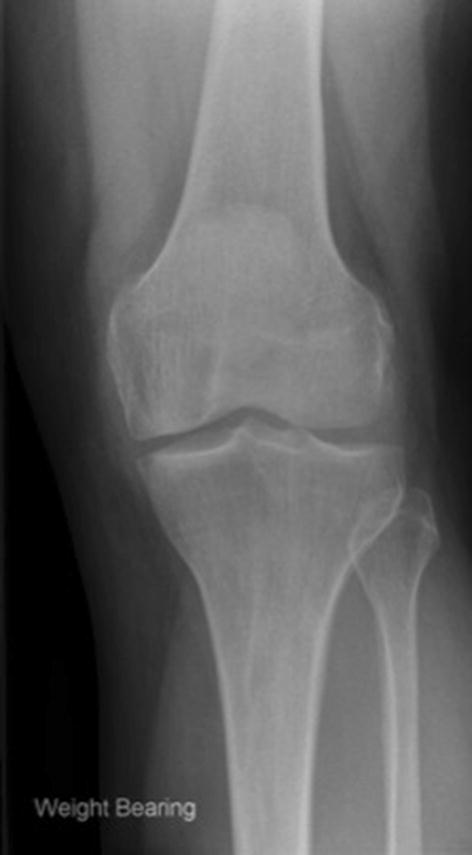

The majority of patients met the indications for surgery (58/83 with preoperative imaging, 70%; Table 1). Twenty-four (29%) did not demonstrate bone-on-bone osteoarthritis. In 16 (19%) the joint space was normal or nearly normal so it was virtually impossible for there to be bone-on-bone (Fig. 2). There were 2 (2%) cases of spontaneous osteonecrosis of the knee, both involving the medial femoral condyle.

Fig. 2.

A preoperative weight-bearing anteroposterior radiograph demonstrating preserved medial joint space. This represents partial thickness cartilage loss and is a contraindication to unicompartmental knee replacement (UKR); UKR performed in these patients have a higher incidence of reoperation, revision and persistent post-operative pain

The indications for mobile-bearing UKR are evidence based, well defined and are based on patho-anatomy. The primary indication is anteromedial osteoarthritis, with bone-on-bone arthritis medially, full thickness lateral cartilage, and functionally intact ligaments [11, 37]. In 29% the pre-operative radiographs did not show bone-on-bone arthritis. In some of these, which had marked joint space narrowing, there may have been true bone-on-bone arthritis, which would have been apparent had a Rosenberg or varus stress radiograph been available. However, in 19% there was virtually full thickness medial joint space and there could not have been bone-on-bone arthritis (Fig. 2). The results of UKR used in this situation are unpredictable and persistent pain, reoperations and revisions are common [9, 27]: In one study, the reoperation/revision rate was about 60% when the pre-operative radiographs showed near normal joint space [27]. In only 3% of cases was the disease more severe than recommended (2% with lateral joint space narrowing and 1% with radiographic evidence of a non-functional ACL). The recommended indications are satisfied in up to 50% of knee replacements [11, 13, 38], yet the NJR shows that UKR is used in only 10% of cases [28]. This study, therefore, suggests that many surgeons are implanting UKR in patients with early disease, without bone-on-bone arthritis, and are not adhering to the recommended indications. These surgeons probably feel that UKR should be used in patients whose disease is not severe enough for TKR. This is not recommended and results in surgeons doing small numbers of UKR and having poor results. UKR should be considered to be an alternative treatment option to TKR for patients with bone-on-bone arthritis. To achieve the best results with the mobile bearing UKR, surgeons should adhere to the recommended indications so they use UKR for at least 20% and ideally about 50% of their primary knee replacements [12].